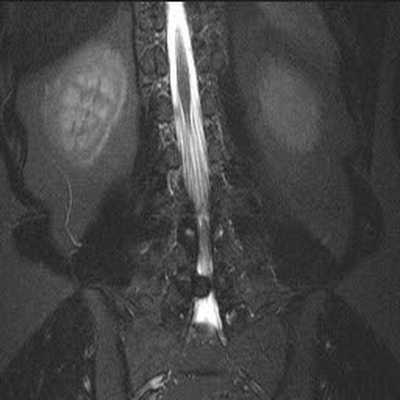

В первом учреждении использовался локатор на весь позвоночник, Т1-, Т2-, STIR-взвешенные изображения в сагиттальной плоскости, Т2-взвешенные изображения в коронарной плоскости (рис. 1). Исследование выполнялось на аппарате Рhilips Intera 1.5Т. Технические параметры импульсных последовательностей представлены в таблице. Технические параметры импульсных последовательностей для МРТ поясничного отдела позвоночника

Рис. 1. МРТ поясничного отдела позвоночника, позиционирование плоскостей. а — позиционирование локатора на весь позвоночник; б — позиционирование сагиттальной плоскости.

Рис. 1. МРТ поясничного отдела позвоночника, позиционирование плоскостей. в — позиционирование аксиальной плоскости; г — позиционирование коронарной плоскости.

Локатор на весь позвоночник использовался только для подсчета количества позвонков. В коронарной плоскости, как правило, использовались Т2-взвешенные изображения, однако при подозрении на недегенеративную спондилоартропатию (например, анкилозирующий спондилоартрит) вместо Т2-последовательности мог быть использован STIR для поиска очагов отека костного мозга в боковых массах крестца и в телах подвздошных костей. Т2-взвешенные изображения в аксиальной плоскости выполнялись единым блоком (около 30 срезов) с включением в зону сканирования не менее 3 межпозвонковых дисков с последующей реконструкцией по плоскости каждого диска (рис. 2). Рис. 2. Реконструкция по плоскости диска из блока аксиальных срезов. При необходимости в рамках одного сбора данных добавлялись короткие блоки по 2—5 срезов на неизмененные сегменты.